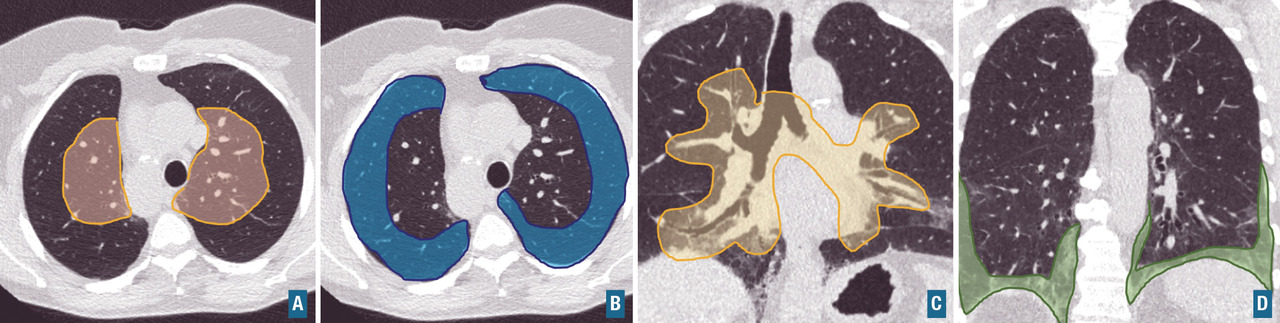

Il s’agit de la pierre angulaire du diagnostic étiologique des pneumopathies interstitielles diffuses. Les modalités de réalisation dans le cadre du diagnostic des pneumopathies interstitielles diffuses sont rappelées dans le tableau 2. L’analyse du scanner thoracique doit décrire le signe radiologique élémentaire prédominant (fig. 2), la distribution des lésions (fig. 3), les anomalies parenchymateuses associées, et les signes extraparenchymateux évocateurs d’un diagnostic : adénopathies médiastinales (sarcoïdose, néoplasie, silicose), érosion des extrémités proximales des clavicules (polyarthrite rhumatoïde), dilatation de l’œsophage (sclérodermie systémique), plaques pleurales (exposition à l’amiante).